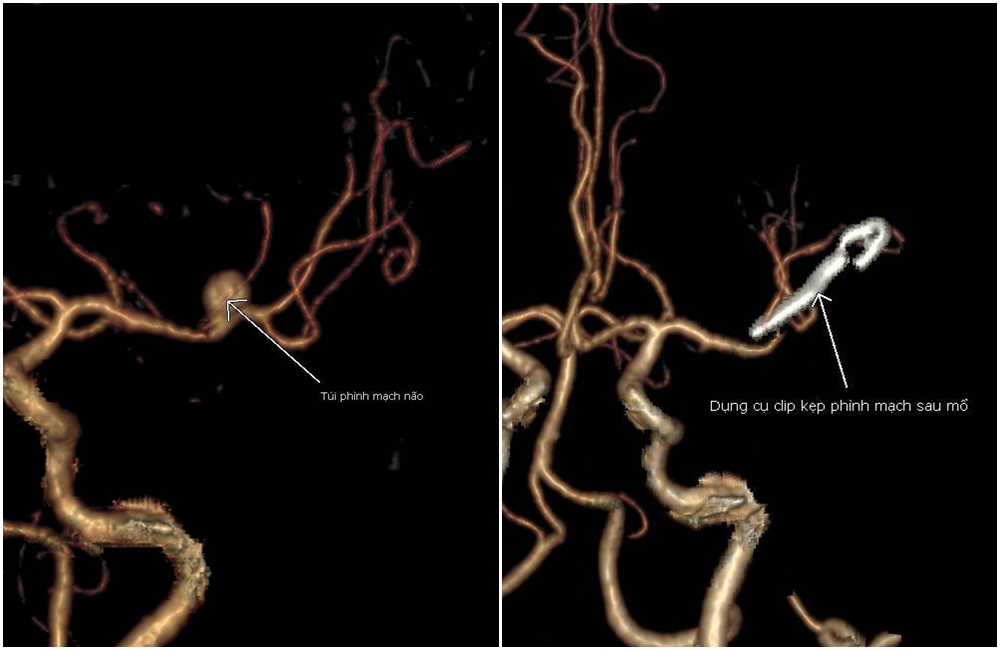

Người bệnh nhập viện trong tình trạng hôn mê, glasgow 12 điểm, liệt nửa người phải. Kết quả chụp cắt lớp vi tính phát hiện ổ xuất huyết lớn bán cầu trái, kích thước khoảng 70x35mm gây đè đẩy đường giữa 8mm. Đồng thời, phát hiện thêm túi phình động mạch não giữa trái, kích thước 5,6x7,1 mm, cổ túi phình 3,3mm.

Hình ảnh ổ xuất huyết não và túi phình động mạch não được xử trí sau phẫu thuật.

Nhận định là ca cấp cứu tối khẩn cấp, bệnh nhân D. xuất huyết nặng nề, chảy máu lan tỏa tràn nhu mô não kèm theo túi phình mạch kích thước lớn, cần phải lựa chọn phương án xử trí để có thể giải quyết được cả hai tổn thương tối ưu.

Sau khi hội chẩn đa chuyên khoa Phẫu thuật thần kinh, Chẩn đoán hình ảnh, Gây mê hồi sức và trao đổi với gia đình, các bác sĩ quyết định kết hợp hai phẫu thuật là: Kẹp túi phình động mạch não giữa bằng clip dưới kính vi phẫu và vi phẫu thuật lấy bỏ ổ máu tụ lớn trong cùng cuộc mổ để cứu bệnh nhân đang trong tình cảnh "ngàn cân treo sợi tóc".

Túi phình mạch não được kẹp bằng clip, ngăn nguy cơ vỡ khối phình mạch.